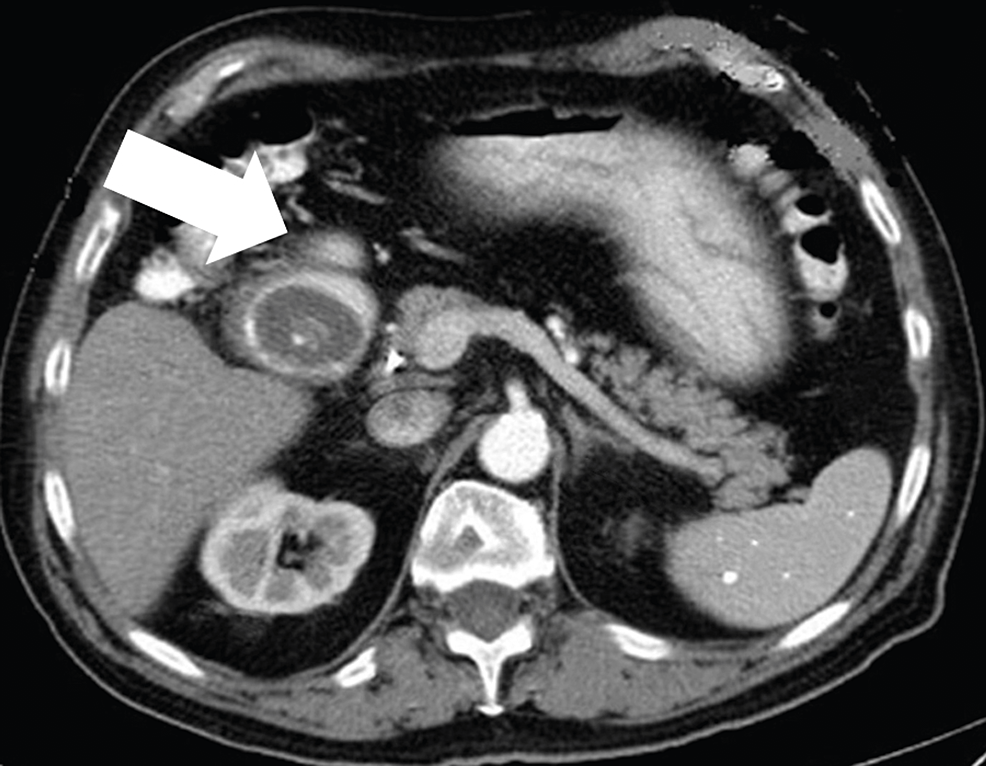

From www.cureus.com

Cureus Bouveret’s Syndrome A Case Series and Literature Review on a Can Gastric Sleeve Cause Gallstones the altered anatomy of the gastrointestinal system after bariatric surgery can affect the flow and storage of bile, further contributing to gallbladder and biliary complications. Other risk factors include a history of gallstones or gallbladder disease before surgery, female gender, older age, and certain medical conditions such as diabetes and. as more patients seeking treatment for their obesity. Can Gastric Sleeve Cause Gallstones.